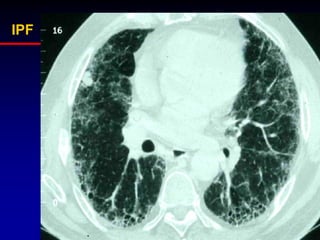

Idiopathic Pulmonary Fibrosis:

typical CT features

• Subpleural/basal

• Fine reticular

• Honeycombing

• Little/no groundglass

HRCT Criteria of IPF

1-reticular abnormality and/or traction

bronchiectasis with basal and peripheral

predominance

2-honeycombing with basal and peripheral

3-atypical features are absent